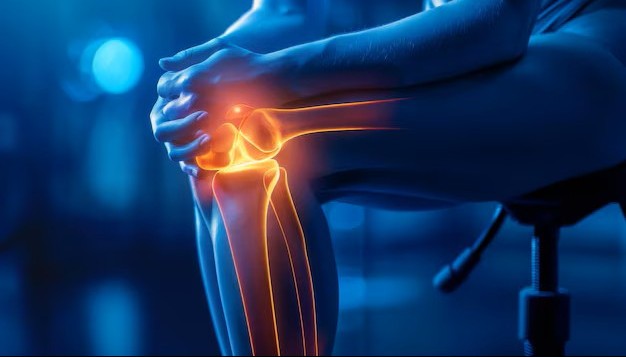

24/7 Accident & Orthopaedic Emergency Care

We specialize in advanced Joint Replacement surgeries, including complex primary and revision procedures. Our team also offers expert care in spine surgery, arthroscopy, limb reconstruction, and pediatric orthopedics — all under one roof.

With modern operation theatres, 24/7 accident & trauma services, ICU, physiotherapy, and full diagnostic support, we ensure patient-centered care with the latest in orthopedic technology.